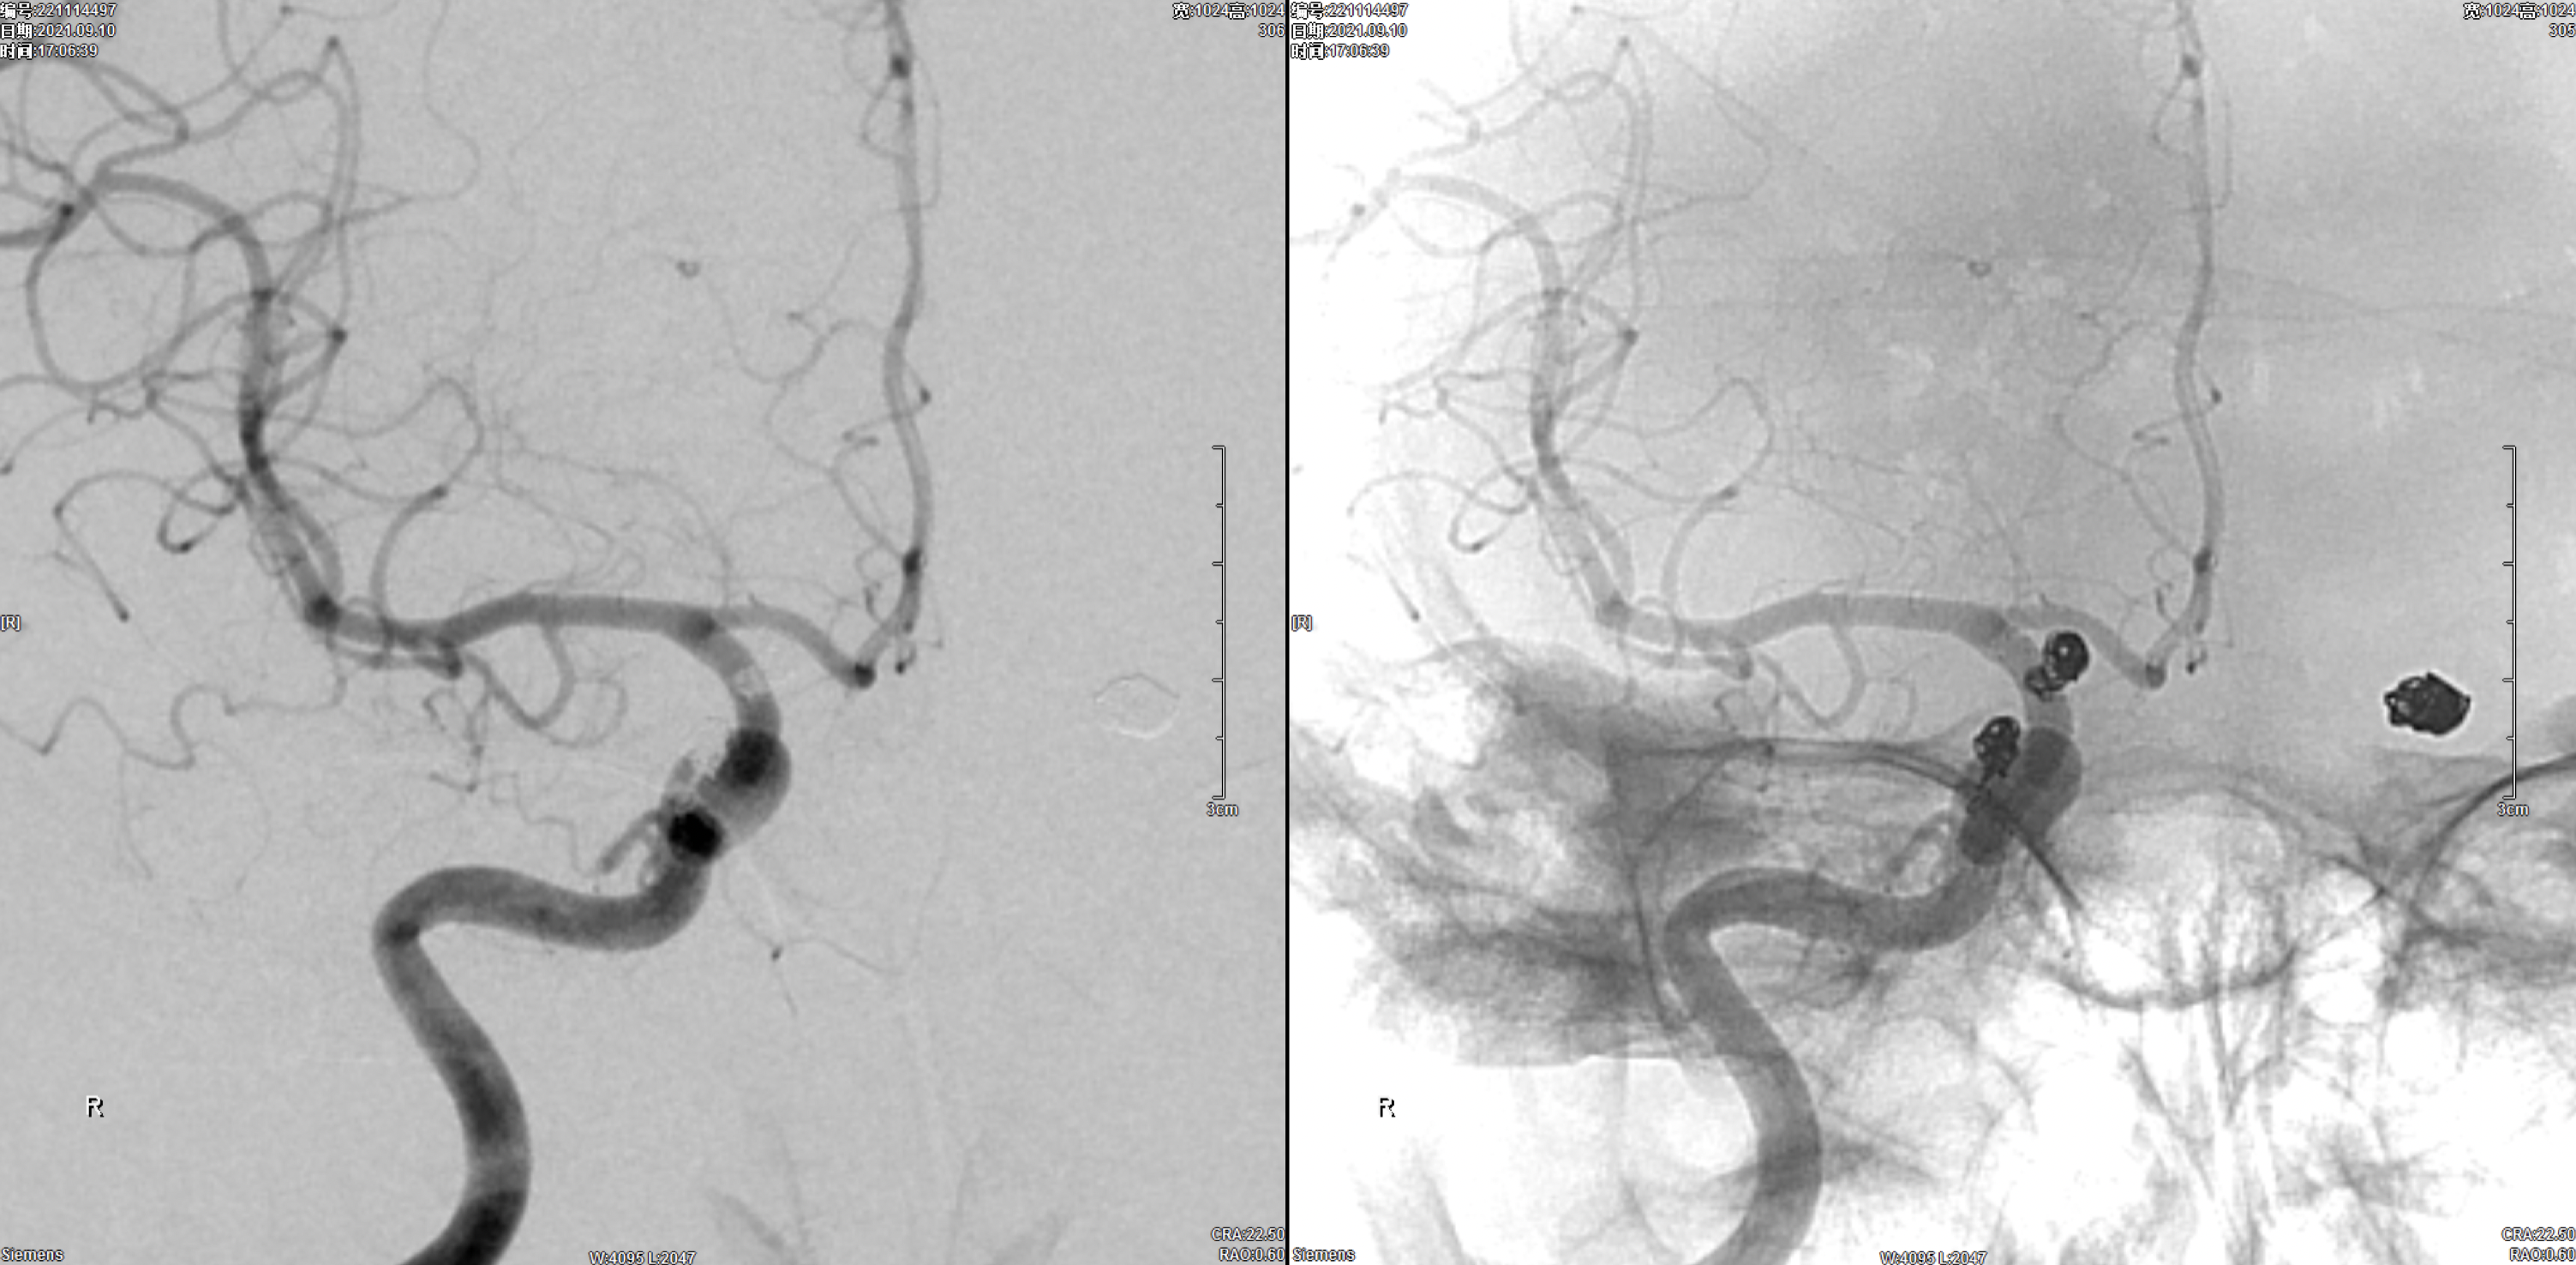

术后3月复查右侧颈内动脉正侧位造影:动脉瘤栓塞满意,未见残留及复发。

术后3月复查左侧颈内动脉正侧位造影:动脉瘤栓塞满意,未见残留及复发。